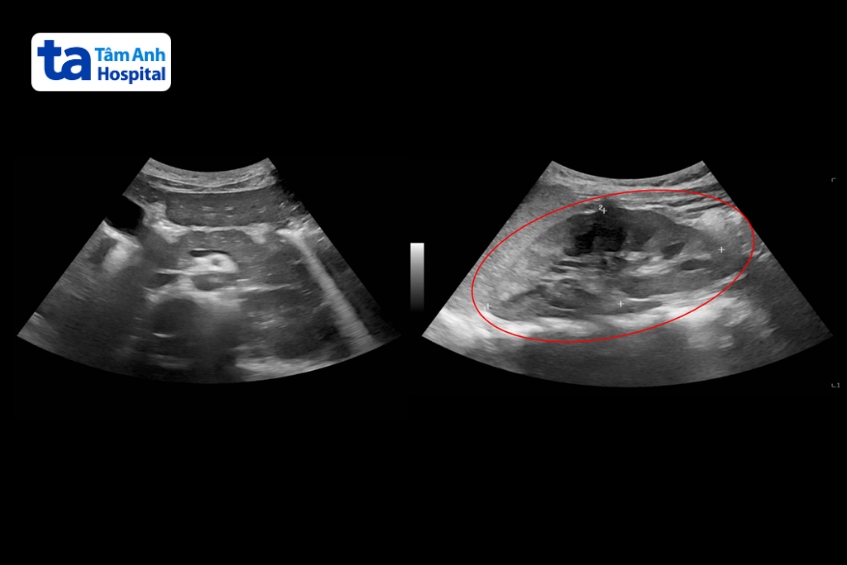

Vài ngày trước, bé đi tiểu màu sẫm, có bọt. Đi khám tại Phòng khám Đa khoa Tâm Anh Quận 7, kết quả xét nghiệm nước tiểu phát hiện đạm niệu cao, có hồng cầu (tiểu ra máu) kèm tổn thương ống thận. Kết quả siêu âm ổ bụng, xét nghiệm lupus ban đỏ, phát hiện bệnh tiến triển nặng khiến thận bị tổn thương, đề nghị sinh thiết để chẩn đoán thêm.